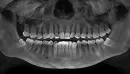

В прошлом году при рассмотрении вариантов ортодонтического лечения обнаружили 2 нижних ретинированных зуба мудрости и один верхний обычный. Практически сразу удалили один нижний с левой стороны (на снимке правый соответственно) и после этого через неделю у стоматолога при лечении одного из зубов, выявила трудности с закрыванием рта. В связи с переездом удаление второго ретинированного зуба отсрочилось. Меня он не беспокоит, точно так же как в принципе ничего на протяжении почти года после удаления не беспокоило.

Недавно я записалась на удаление второго нижнего зуба, но по какой-то причине состояние суставов резко усугубилось буквально несколько дней назад. На протяжении нескольких дней чувствовала заклинивания челюсти при зевании или при визите к стоматологу, движение челюсти неровное, как будто что-то смещается, иногда было даже при открывании рта до среднего уровня. Сегодня добавилась ноюще-давящая боль в области лица и ощущение слабости при жевании. Когда точно начались проблемы с суставами я не могу сказать, возможно где-то иногда и чувствовала какой-то дискомфорт, но меня это не беспокоило и внимания я не обращала. Такого как сейчас не было никогда.